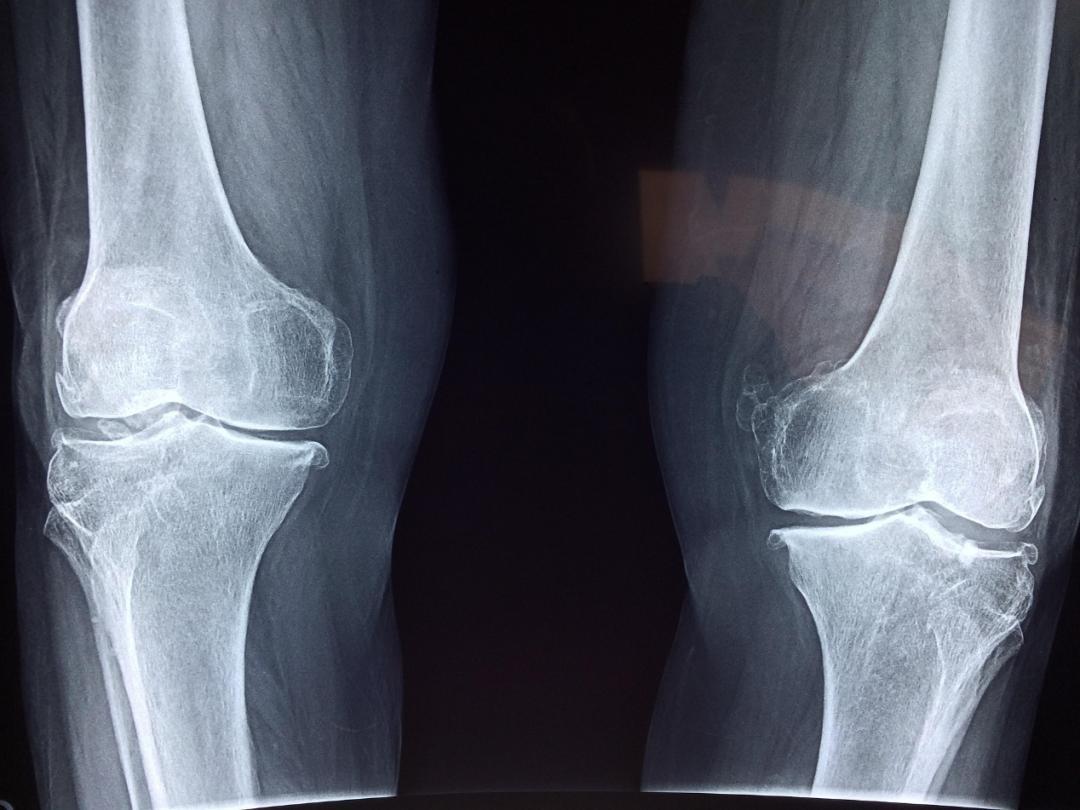

2 司美格魯肽或可用於治療骨關節炎

代謝紊亂已被公認爲是骨關節炎(osteoarthritis,OA)發生和進展的主要因素。尋找新的治療藥物來改善OA中的代謝紊亂至關重要。近日,中國科學院深圳先進技術研究院Liping Tong團隊發現,胰高血糖素樣肽-1受體(GLP-1R)激動劑司美格魯肽(semaglutide,SG)在肥胖的OA小鼠模型中表現出強烈的軟骨保護作用。具體來講,司美格魯肽可以明顯改善動物的軟骨退化、骨贅形成、滑膜損傷和疼痛敏感性等病理指標。一項20人蔘與的小規模隨機試點臨牀研究(ChiCTR2200066291)進一步支持了上述觀點。研究人員還發現,司美格魯肽對關節的保護作用與減重並無關聯,而是通過調節“GLP-1R-AMPK-PFKFB3”軸,在炎症條件下將軟骨細胞代謝譜從糖酵解重新編程爲氧化磷酸化,從而實現軟骨修復。詳細數據於2月9日發表在《細胞·代謝》(Cell metabolism)雜誌。